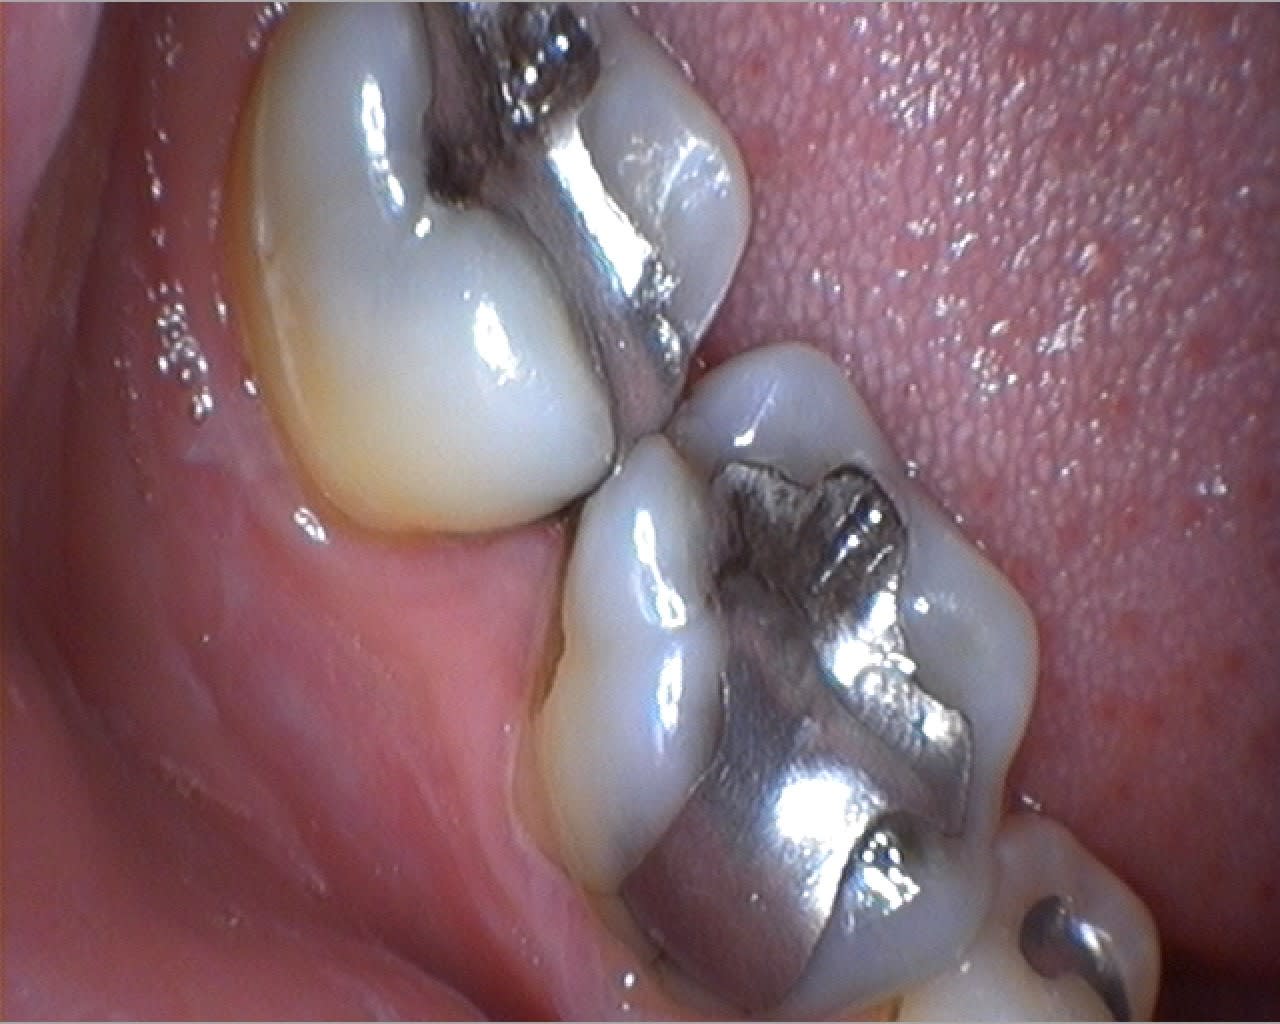

Quelques photos prises ce matin au cours d'une longue séance de soins. Je posterais un test complet de la caméra bientôt pour ceux que ça intéresse...

On est bien d'accord Pluton, c'est de la merde, mais immédiate en acquisition et très pratique pour caser une CCM !

C'est un peu comme comparer une Rx argentique et une RVG.

J'ai remonter le post pour un copain nonolien qui voulait savoir comment on gère le double mélange à l'Impregum. Simplement pour montrer le berceau gingival sans saignement.